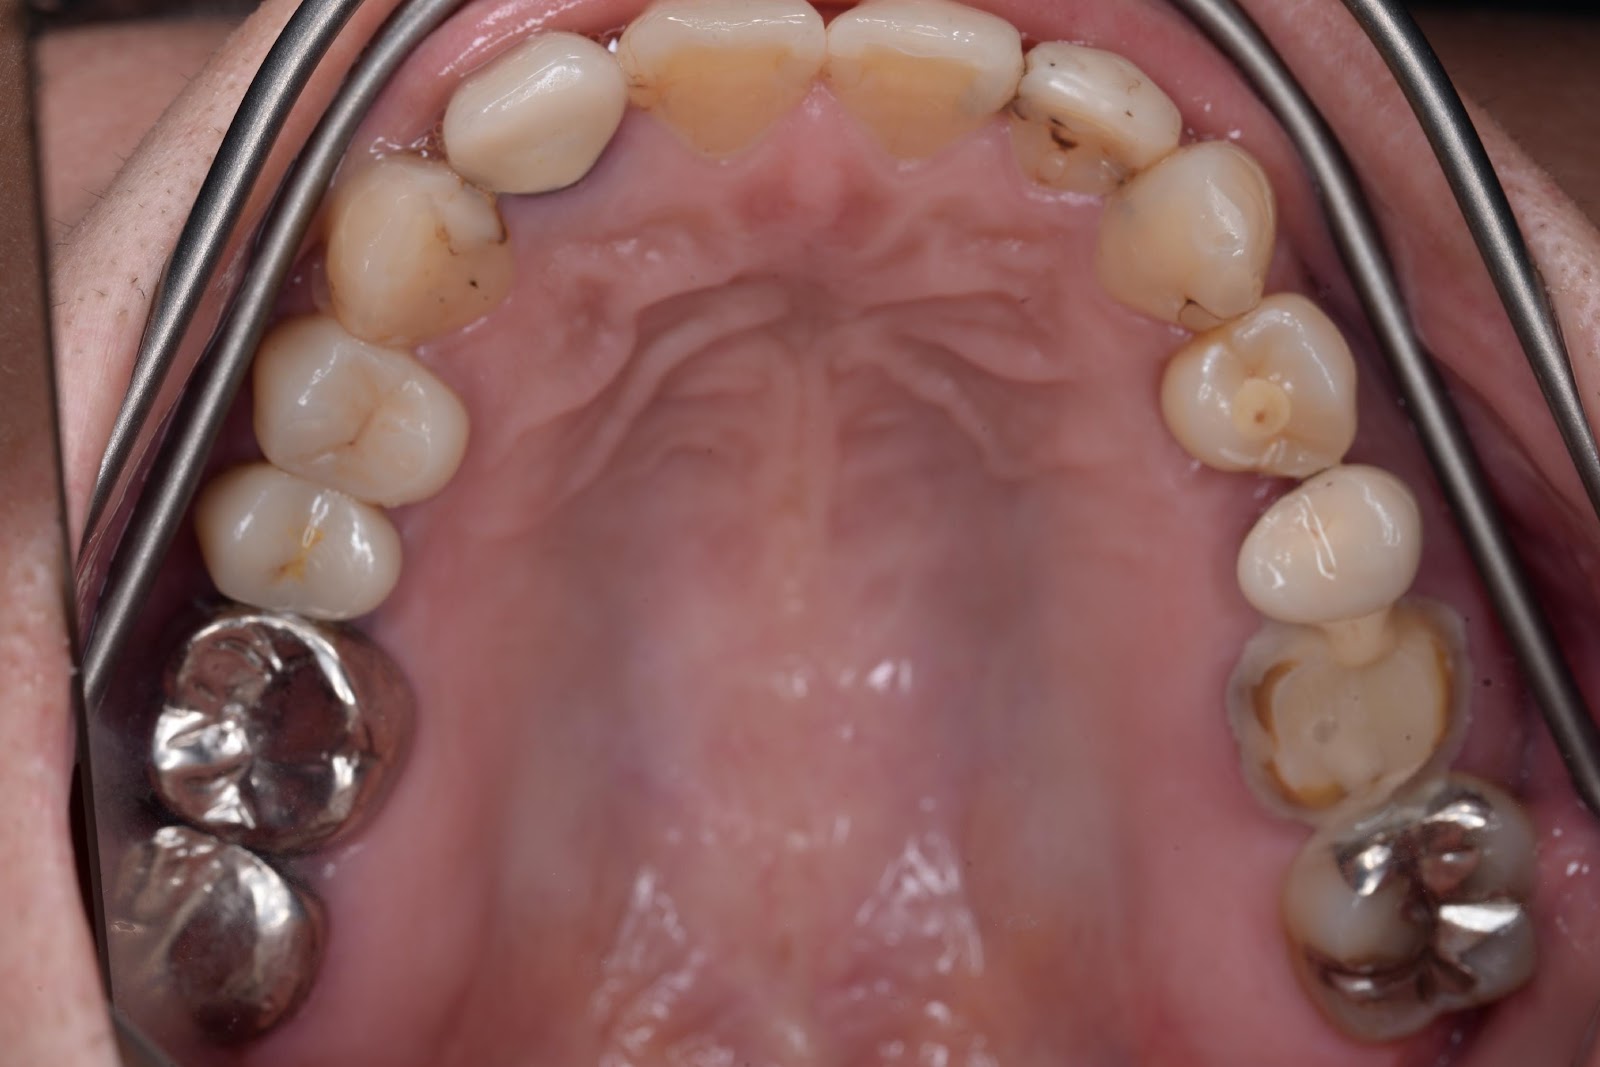

上部構造セット後

CASE-1左上の小臼歯部 インプラント埋入 1本

50代 女性